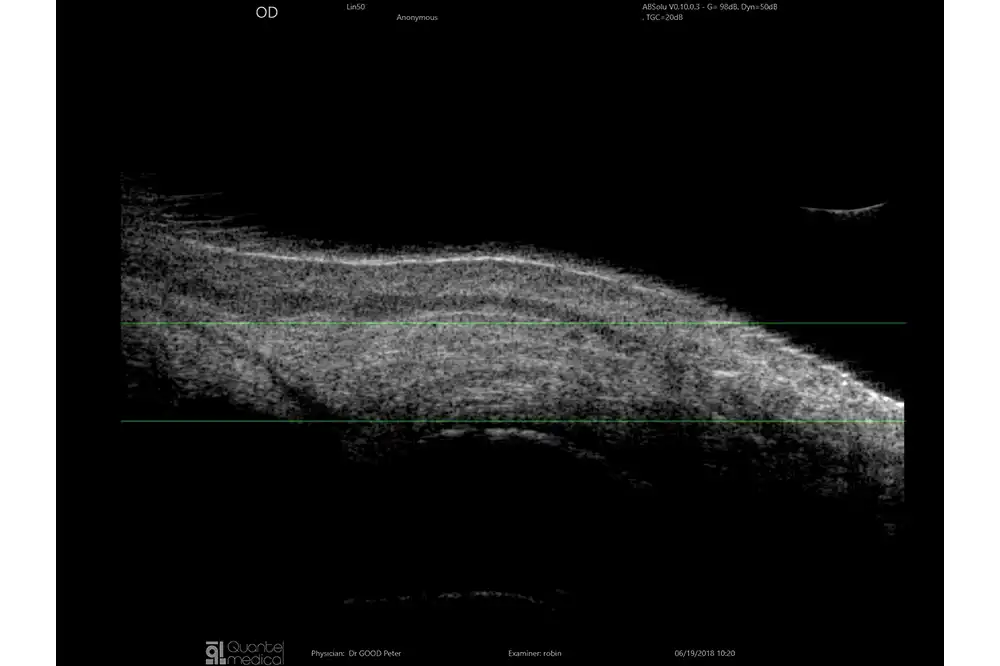

Verlengde scherptediepte van 70%

De ringtechnologie verdubbelt praktisch de scherptediepte. De 20 MHz-ringvormige sonde heeft een verlengde scherptediepte van 70%, waardoor het mogelijk is om pathologieën van het glasvocht, het netvlies en verder tegelijkertijd te observeren zonder concessies te doen aan de beeldresolutie.